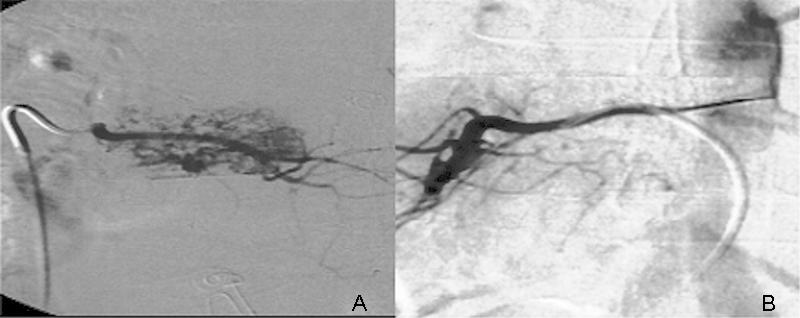

Vertebral hemangiomas are benign lesions accounting for 2 to 3% of all spinal tumors. They are usually asymptomatic and found incidentally on imaging. Uncommonly, vertebral hemangiomas with significant epidural extension can result in radiculopathy or spinal cord compression. Decompressive surgery with or without stabilization is often required when neurological deficits are present. However, surgery can be associated with massive hemorrhage as these tumors are hypervascular. Preoperative embolization and sclerotherapy are well-known management strategies used to minimize intraoperative bleeding and improve symptoms. Recently, the use of sclerosants such as ethanol has decreased, due to reported complications such as Brown-Sequard syndrome. We describe the use of sodium tetradecyl sulfate (Fibro-Vein™, STD Pharmaceutical, Hereford, UK) as an effective alternative to ethanol in the preoperative management of vertebral hemangiomas. To our knowledge, this has not been previously reported. In three patients, we demonstrated minimal intraoperative blood loss using a combination of preoperative embolization of arterial feeders and sclerotherapy with sodium tetradecyl sulfate to control and secure venous drainage. No patients developed complications related to the procedure. In addition to minimal blood loss, a clear dissection plane was also noted intraoperatively.